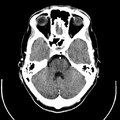

Computed tomography of human brain, from base of the skull to top. Taken with intravenous contrast medium.